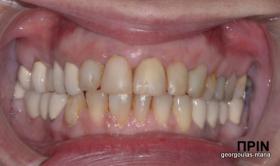

ΟΛΙΚΗ ΑΠΟΚΑΤΑΣΤΑΣΗ ΑΝΩ ΓΝΑΘΟΥ

Η ασθενής ήταν δυσαρεστημένη από την εμφάνιση των άνω δοντιών της. Ήθελε τα δόντια της να αποκτήσουν ομοιόμορφο, πιο λευκό χρώμα κ να αποκτήσει ένα πιο αρμονικό χαμόγελο με φυσική εμφάνιση. Λόγω των εκτεταμένων εμφράξεων σύνθετης ρητίνης στα πρόσθια δόντια, των εμφράξεων αμαλγάματος στα πίσω αριστερά δόντια αλλά και της υπάρχουσας γέφυρας στα πίσω δεξιά δόντια, και σε συνδυασμό με την επιθυμία της ασθενούς για φυσικό αποτέλεσμα αποφασίστηκε η τοποθέτηση ολοκεραμικών στεφανών στα δόντια της άνω γνάθου. Στη θέση του δεύτερου προγομφίου δεξιά τοποθετήθηκε εμφύτευμα. Πραγματοποιήθηκε περιοδοντική θεραπεία, ενδοδοντικές θεραπείες (απονευρώσεις) κ τοποθετήθηκαν ενδορριζικοί άξονες υαλονημάτων  όπου κρίθηκε απαραίτητο. Σε όλη τη διάρκεια της θεραπείας η ασθενής ήταν καλυμμένη αισθητικά κ λειτουργικά με προσωρινές αποκαταστάσεις.